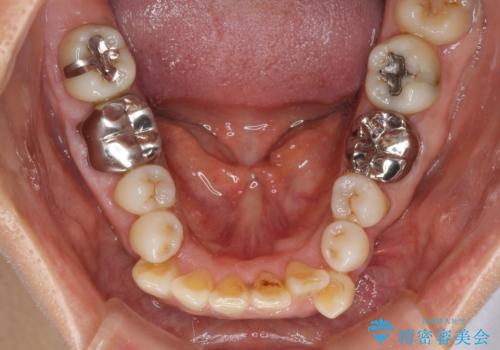

- 八重歯やクロスバイトを気にして来院された患者様です。

口元の突出感はありませんでしたが、デコボコが強く、非抜歯矯正とすると出っ歯仕上がりとなる可能性があったため、上下左右の第一小臼歯4本を抜歯し、ワイヤー装置にて矯正治療を行うこととしました。